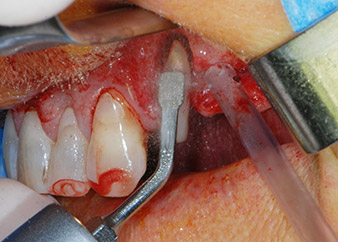

периодонциум

Фиг. 4: За да се съхрани зъбът като временен абатмънт, периодонциумът е изпилен с пиезохирургично оборудване...

Въпреки това, ние се придържахме към първоначалния си план да запазим и двата зъба като абатмънти за временен мост по време на 6-месечната остеоинтеграция на имплантите. При повторна интервенция, ситуацията трябва да се преразгледа. Първо, в опит да се овладее ендо-перио проблема, останалата повърхност на зъба е внимателно обработена с пиезохирургично оборудване (Piezomed, W&H, използван с накрайник S1 под формата на шпатула, първоначално проектиран за ерозия на латералната синусна стена) (Фиг. 4).